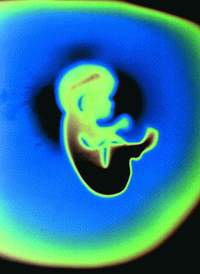

他用一只小脚试试胎盘那柔软似枕头的组织,他像一只被脐带系在岸边的小船。他喝了一些羊水,那味道有点像海水。他咽了下去,打了一阵嗝。他妈妈觉得他似乎在微微地有节奏地跳动。

他不再打嗝了,又舒服地用自己喜欢的姿势呆在子宫里——臀部抵在妈妈的肋骨上,背朝着她的左侧,又打起了瞌睡。

胎儿就像即将去参加运动会的运动员一样,为了出生后的生活进行训练。他不需要呼吸,但是膈肌却照样练习呼吸动作。他除了喝羊水以外,不吃不喝。

羊膜囊像个水泡似地包围着他,使胎儿免受震荡和气温的变化。它很滑润,使胎儿可以自由活动,这对骨骼和肌肉的发育是至关重要的。